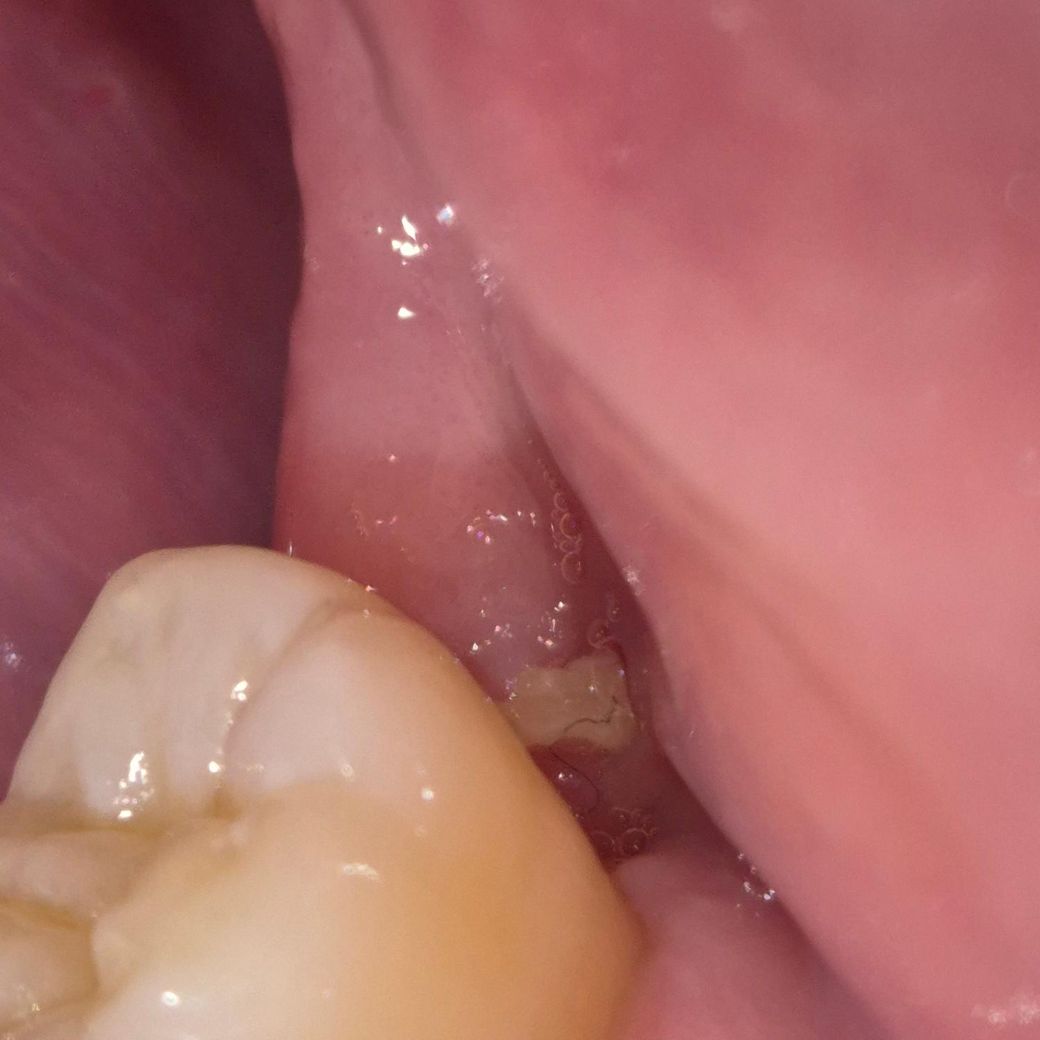

사랑니 발치 후 흰색 이(?) 보입니다.

사랑니 발치한지 3개월쯤 됩니다. 최근에 발치한 곳 혓바닥으로 만져보니 뭔가 느껴저서 사진 찍어봤습니다. 이게 뭘까요????

위 사진만으로는 명확히 파악하기는 어렵습니다. 뼈가 남아서 그렇게 보일 수도 있을 것 같습니다

아주 단단한 모양새면 남아있던 치아 뿌리 조각, 부골 등일 수 있고 그게 아니면 치유부전으로 인한 염증조직같습니다

잇몸이 아물면서 생기는 자연스러운 현상입니다. 큰 문제가 잇는건 아니니 걱정하지 않으셔도 됩니다.

사랑니를 발치하고 나면 발치한 부위에 가피등이 형성되며 흰색으로 보일수 있습니다 문제가 있는것은 아니며 발치한 부위가 자극이 되지 않도록 하는것이 중요합니다.